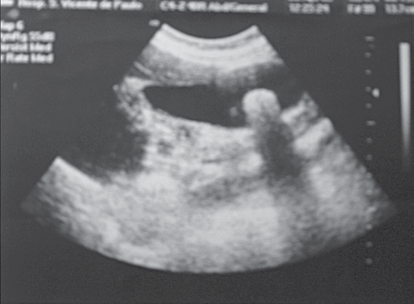

Observe a imagem.

Paciente masculino, 36 anos, apresenta o exame mostrado na imagem.

A imagem é compatível com